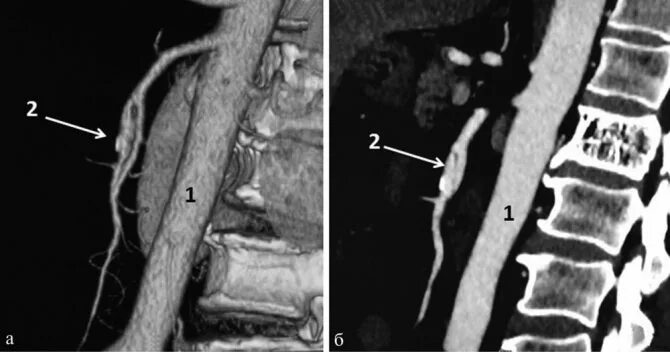

Кальциноз брюшного отдела